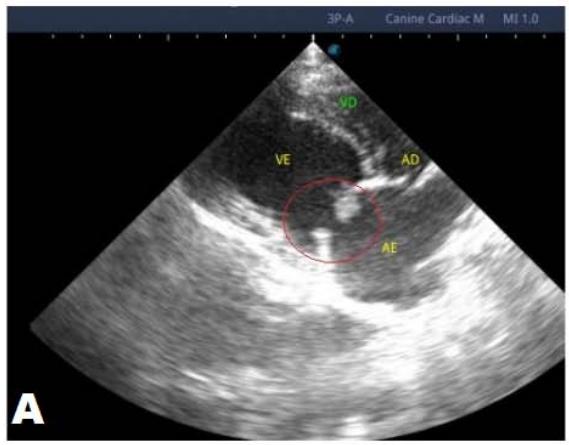

One year later, the animal returned for a new evaluation, repeating the ECHO (Figure 2), which showed the progression of the increase in the left atrium. The electrocardiogram (ECG) (Figure 3) shows baseline sinus arrhythmia with the presence of a premature ventricular complex (Figure 4). Owners report drowsiness, hyporexia, and syncope. However, they did not present tiredness or cough. Blood pressure was 80 mmHg.

Figure 2: Echocardiogram (2022): observed increase in the left atrium and ventricle; thickened/degenerated mitral valve (A); observed in a Doppler study, turbulent systolic flow within the left atrium, characterizing significant mitral valve insufficiency (B); systolic turbulent flow within the right atrium, representing mild tricuspid valve insufficiency (C); hemodynamic assessment - maximum velocity gradient mitral regurgitation: $3.51\mathrm{m / s} / 49.22\mathrm{mmHg}$; observed left ventricular diastolic dimension above normal limits with normal systolic function parameters, characterizing systolic dysfunction; preserved diastolic function

In 2022, the animal returned for annual exams one year after the diagnosis. The ECHO showed an increase in the left atrium and ventricle, thickened/degenerated mitral valve (Figure 2), preserved diastolic function, and low probability of pulmonary hypertension; the ECG detected an increase in the duration of the P wave and the QRS complex (Figure 3), suggestive of atrial and left ventricular overload, baseline sinus arrhythmia with the presence of a premature ventricular complex.